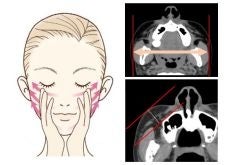

図1 今回のフェイシャルマッサージによるたるみ改善効果

起きた状態で撮影したCT画像を用いて試験前後の変化を解析したところ、同一部位における脂肪層の厚みが平均で約0.8mm減少(平均3.7%減少)していることが分かりました(図3)。また、頬の最も高い位置は試験前よりも平均で約2.7mm上方向に移動していることが明らかになりました(図1)。このことから、本マッサージはたるみ改善や頬のリフトアップに寄与していることが分かりました。